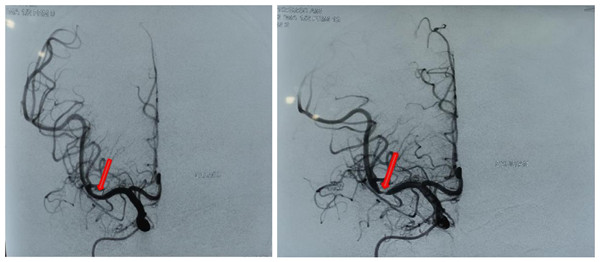

患者中年男性,1月因胸闷、气短来我院心外科就诊,入院诊断为主动脉瓣关闭不全,同时患者合并右侧大脑中动脉重度狭窄,需行体外循环心脏瓣膜置换术,但考虑到手术时间长,体外循环时脑灌注压低有可能使脑缺血加重发生肢体瘫痪,决定先治疗大脑中动脉狭窄,遂转入神经内科。行脑血管造影提示右侧大脑中动脉重度狭窄,具有明确的手术指征,需在全麻下行右侧大脑中动脉狭窄支架植入术。但考虑到患者有主动脉瓣关闭不全合并双侧大量胸腔积液、重度阻塞性通气功能障碍,心肺功能差,麻醉及手术风险极高,遂请心内科、心外科、呼吸内科、麻醉科等多学科进行全院讨论,一致认为患者病情复杂,手术风险高,围手术期随时可能发生呼吸循环衰竭、脑梗死等各种意外,术前需加强强心、利尿、吸氧等改善心肺功能。最终,在各科室的共同努力和密切配合下,神经内科张茹副主任和张宏医师成功实施了手术。术后患者生命体征平稳,未诉不适。